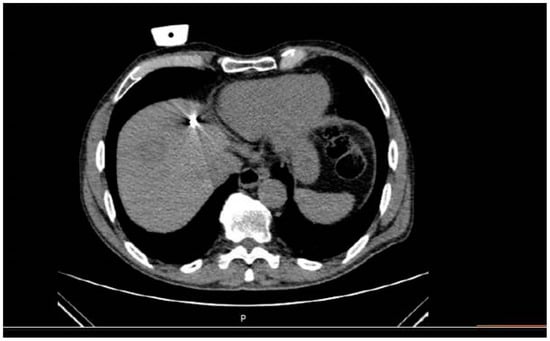

Trajectory planning and insertion of the microwave antenna were conducted using a commercially available navigation system for interventional radiology (IMACTIS SAS, Saint Martin d’Hères, France), (Figure 1). Educating the patient for correct breathing is of outmost importance; in the present study, all scans (both set-up and control ones) as well as needle movements were performed in the end-expiration apnea. In all lesions included in the present study, ablation was performed using a single microwave antenna. Once in the correct location, the ablation session was set up and performed according to the coagulation charts provided by the manufacturer in consideration of the tumor size and location and the desired safety margin. In all sessions, track ablation was performed during antenna removal from the liver in order to reduce potential risk of bleeding and peritoneal tumor seeding. CT scan in the arterial and portal venous phases validated the ablation zone and evaluated any potential immediate complications at the end of the MWA treatment (Figure 2). All patients were hospitalized overnight.

Figure 1. A 65-year-old male patient with colorectal cancer located at left colon with 2 synchronous metastatic lesions at hepatic dome (segment VIII). Stereotactic CT-guided ablation post systemic chemotherapy, and prior to colon resection was performed with the patient in supine position, through the anterolateral approach, under iv analgesia. Upper row: Planning scan for designing the trajectory of approach (orange line) using the IMACTIS CT navigation system. Lower row: Control scan evaluating the antenna’s position in the target lesion using the IMACTIS CT navigation system.